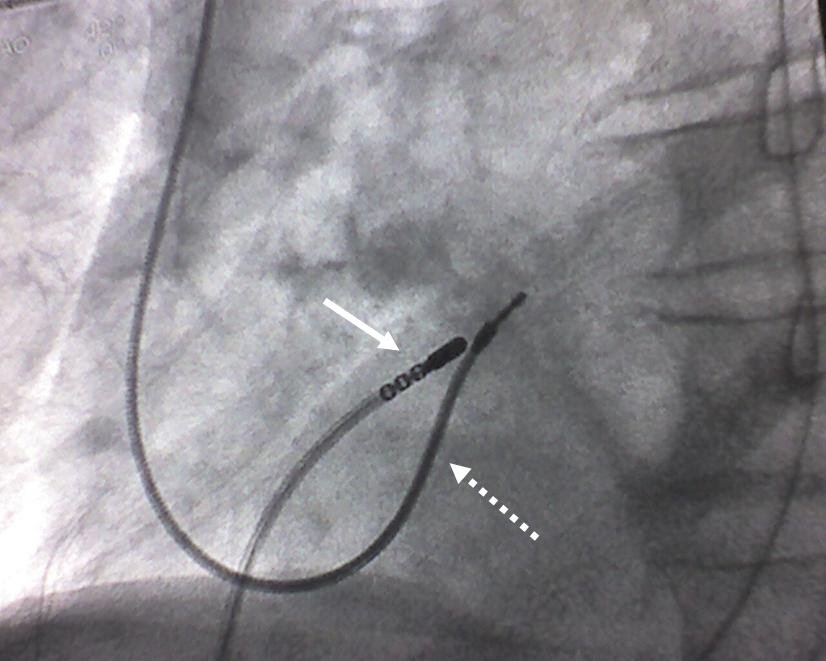

Simultaneous atrioventricular node ablation and leadless pacemaker What Is Av Node Ablation in patients with atrial fibrillation (af), the ventricular rate is determined in large part by the conduction properties of. what is an av node ablation? av node ablation is a procedure that damages the tissue that sends electrical signals from your upper chambers to your. what is av node ablation and how will a pacemaker help?. What Is Av Node Ablation.